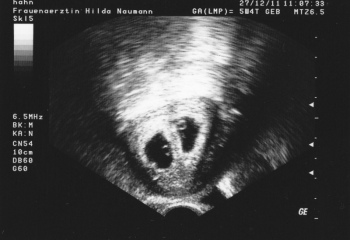

БЕРЕМЕННОСТЬ И РОДЫ